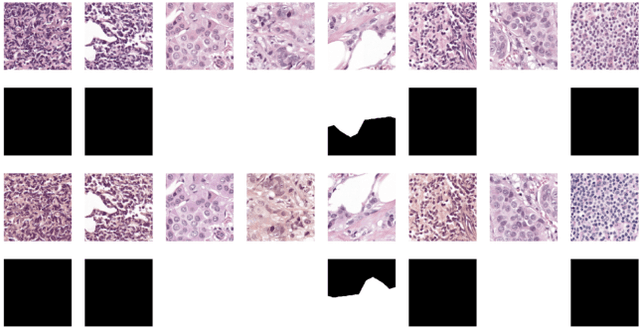

Detection and Classification of Breast Cancer Metastates Based on U-Net

Sep 09, 2019

This paper presents U-net based breast cancer metastases detection and classification in lymph nodes, as well as patient-level classification based on metastases detection. The whole pipeline can be divided into five steps: preprocessing and data argumentation, patch-based segmentation, post processing, slide-level classification, and patient-level classification. In order to reduce overfitting and speedup convergence, we applied batch normalization and dropout into U-Net. The final Kappa score reaches 0.902 on training data.